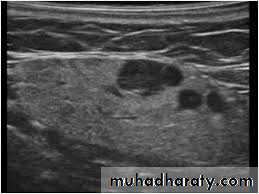

1. For detection of cervical lymphadenopathy.2. Examination of various masses including thyroid gland, abscess, salivary glands.

3. Vascular abnormalities (Doppler US)

4. Aids in differentiation of solid or cystic masses.

5. Valuable for guided fine needle aspiration biopsy (FNA).